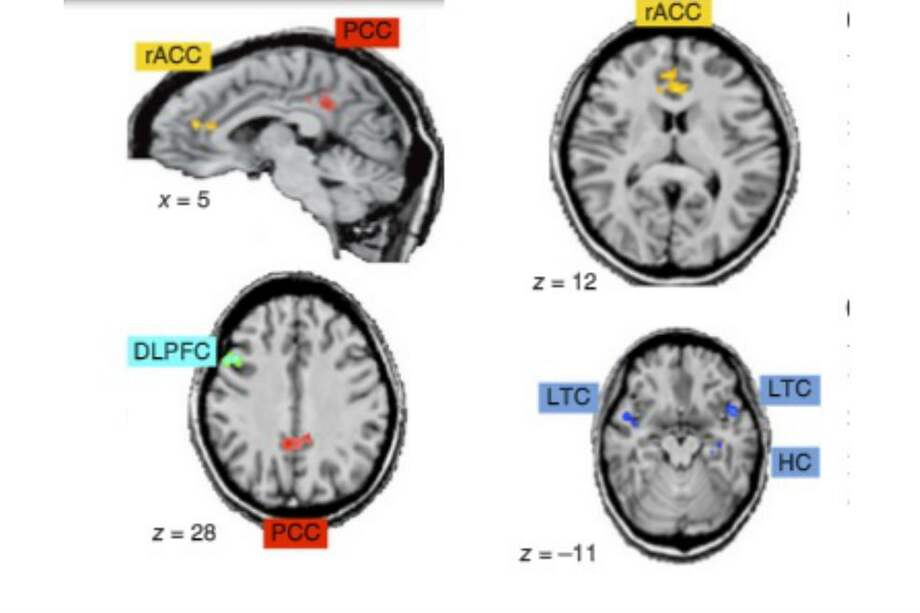

Aunque a simple vista parece un experimento simple, con ese ensayo, en el que se utilizaron técnicas de neuroimagen como la resonancia magnética funcional, Tanaka logró identificar por primera vez, dónde está ubicado el centro estratégico del cerebro.

En términos técnicos esas estrategias se desarrollan en el giro cingulado, una zona alargada que está en la mitad de dos hemisferios y a unos tres centímetros bajo el cráneo. Su parte anterior (que está más cerca de la frente) es la que controla las estrategias defensivas y su parte posterior representa la estrategia ofensiva.